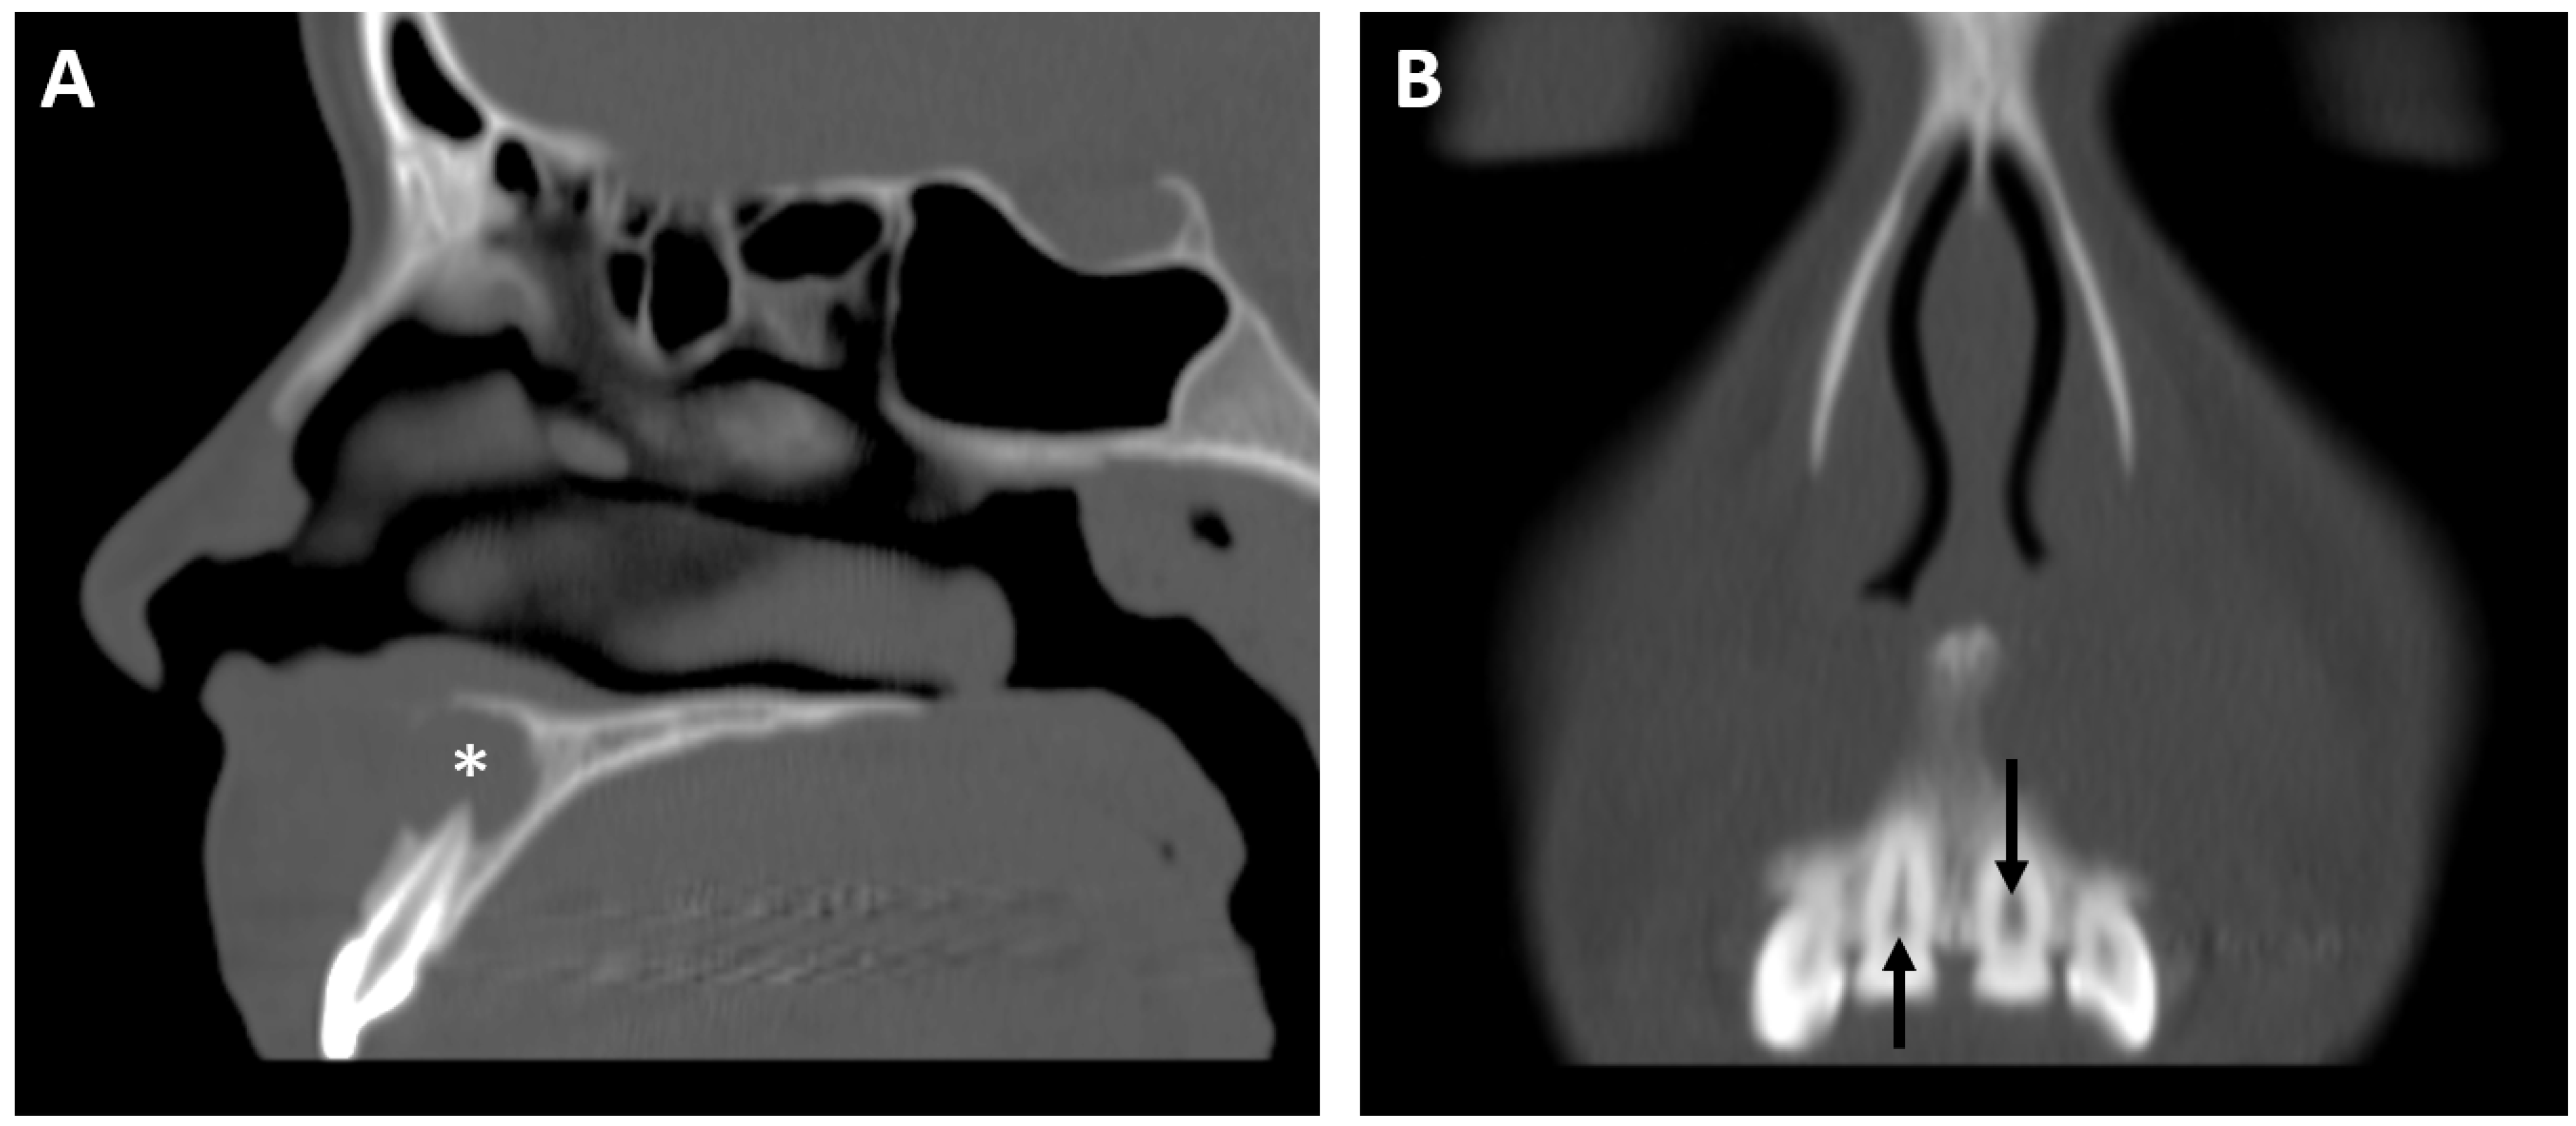

3.3. Radiologic Correlations of Embryological Development

3.5.2. Dental Decay Radiologic Correlations